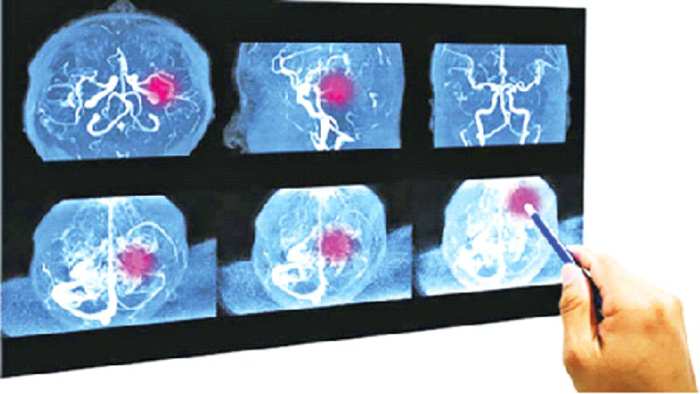

মস্তিষ্কের রক্তনালির এনজিওগ্রামকে ডিএসএ বা ডিজিটাল সাবট্রাকশন এনজিওগ্রাম বলা হয়।

lরোগ নির্ণয়: মস্তিষ্কের রক্তনালির রোগ (যেমন– রক্তনালি বন্ধ হওয়া বা ইস্কেমিক স্ট্রোক, রক্তনালি ফেটে যাওয়া বা হেমোরেজিক স্ট্রোক, অস্বাভাবিক সংযোগ) সঠিকভাবে নির্ণয় করা।